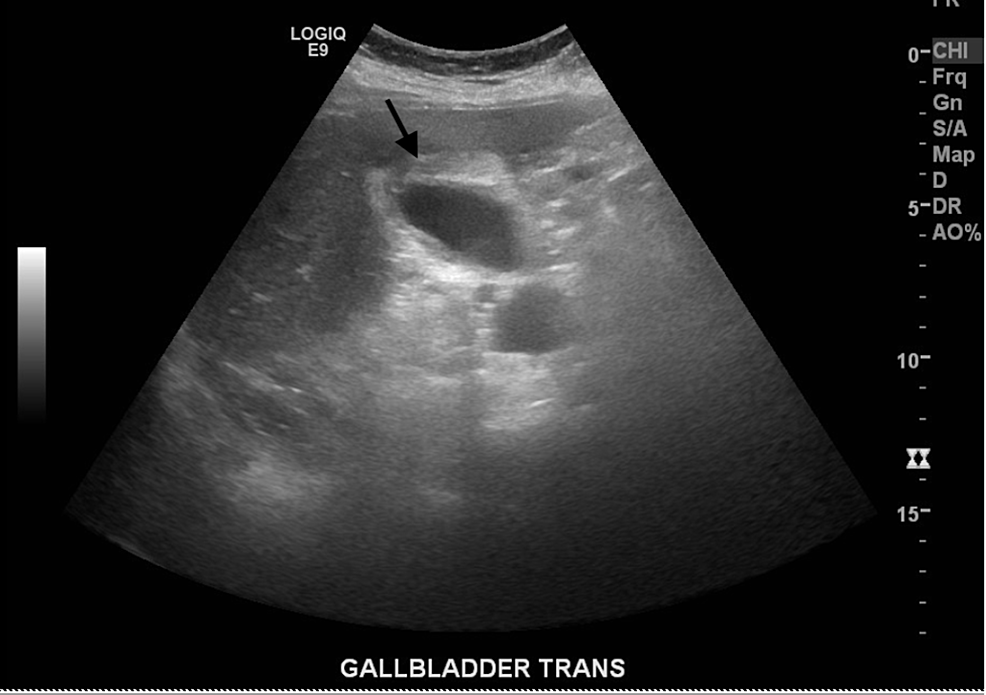

Ultrasound of images gallbladder fossa mimics a gallbladder Radiology

Ultrasound of images gallbladder fossa mimics a gallbladder Radiology Fluid Collection Gallbladder Fossa ct image shows collection of hypoattenuating fluid and air (arrow) in gallbladder fossa. endoscopic gallbladder drainage is a feasible and efficacious alternative to percutaneous drainage in the management of acute cholecystitis for. collections of fluid in the gallbladder fossa can be detected by ultrasound in as many as 29% of patients following. the role of imaging. Fluid Collection Gallbladder Fossa.

Gallbladder Fossa Gallbladder Fluid Collection Gallbladder Fossa collections of fluid in the gallbladder fossa can be detected by ultrasound in as many as 29% of patients following. endoscopic gallbladder drainage is a feasible and efficacious alternative to percutaneous drainage in the management of acute cholecystitis for. the role of imaging is to establish the diagnosis, delineate the extent of injury, and plan appropriate intervention.. Fluid Collection Gallbladder Fossa.